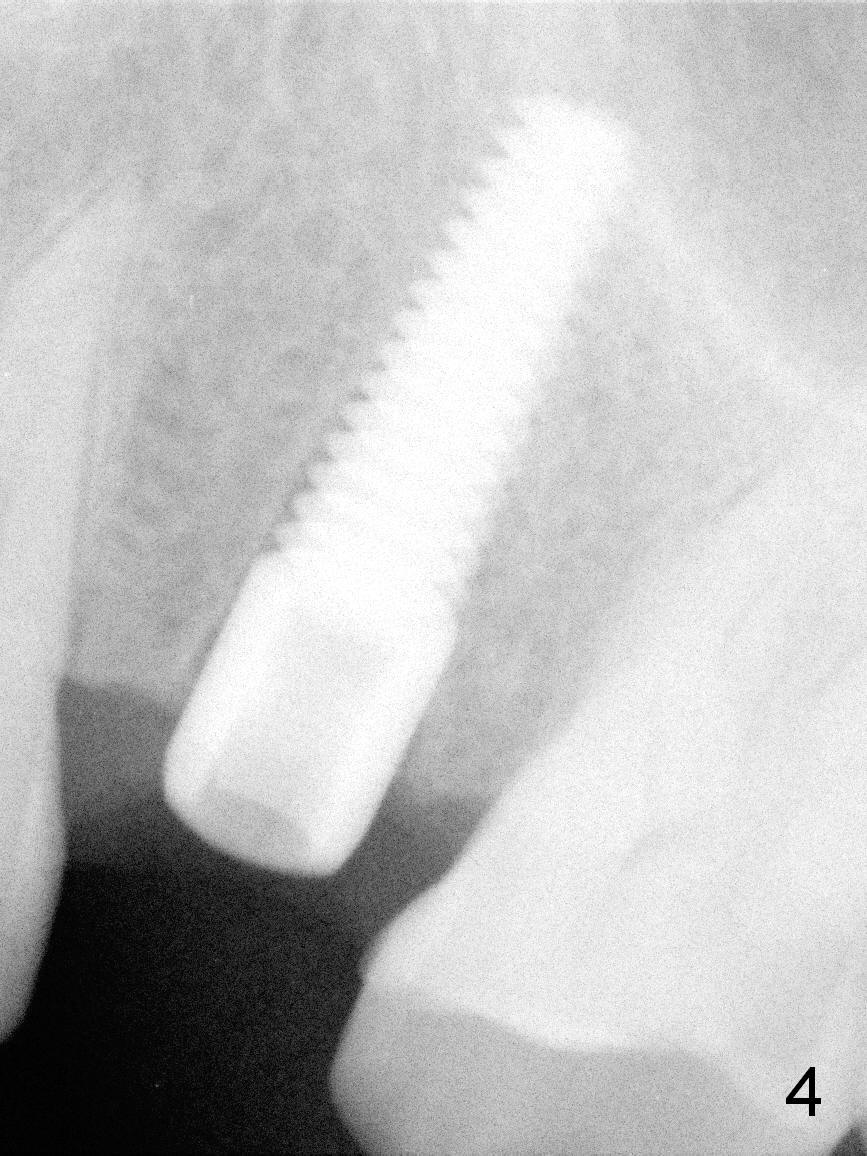

A 47-year-old man returns to clinic with chief complaint "top left tooth chips". Exam reveals subgingival fracture of the lingual cusp of the tooth #13 (Fig.1). A 4.5x17 mm tissue-level implant and 3.5x3 mm abutment appear to be appropriate for the site (Fig.2 (^: sinus floor)). After extraction and socket treatment with 1:50,000 Epinephrine gauze, a 4.5x20 mm tap is placed at the depth of 17 mm. Although the tap has achieved stability, a PA taken with it does not the superior end due to the interference of its long handle (Fig.3 H). A dummy implant (4.5x17 mm) is placed to show its approximation to the sinus floor (Fig.4). After removal of the dummy implant, the definitive implant is placed with certainty with the planned abutment (Fig.5 A). An immediate provisional is placed after bone graft and membrane.